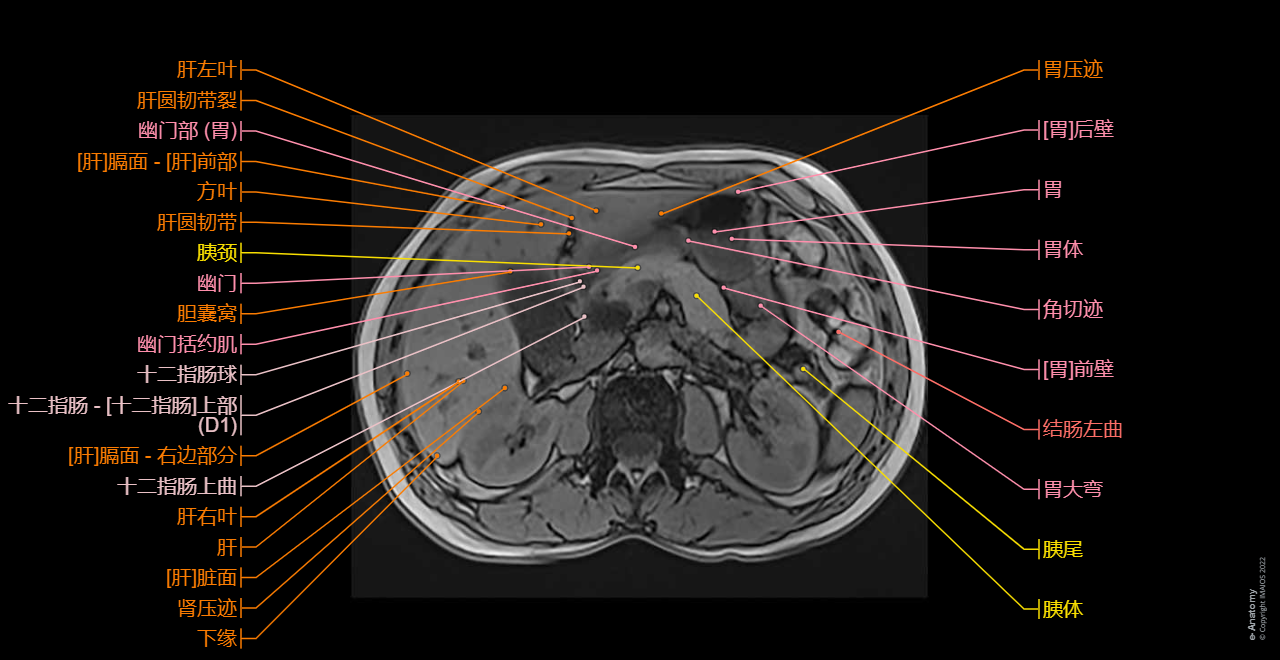

Axial T1 in-phase and axial T1 out-of-phase on the liver: Conventional abdominal MRI imaging to study extraductal structures (hepatic segments, pancreas, spleen, kidneys)